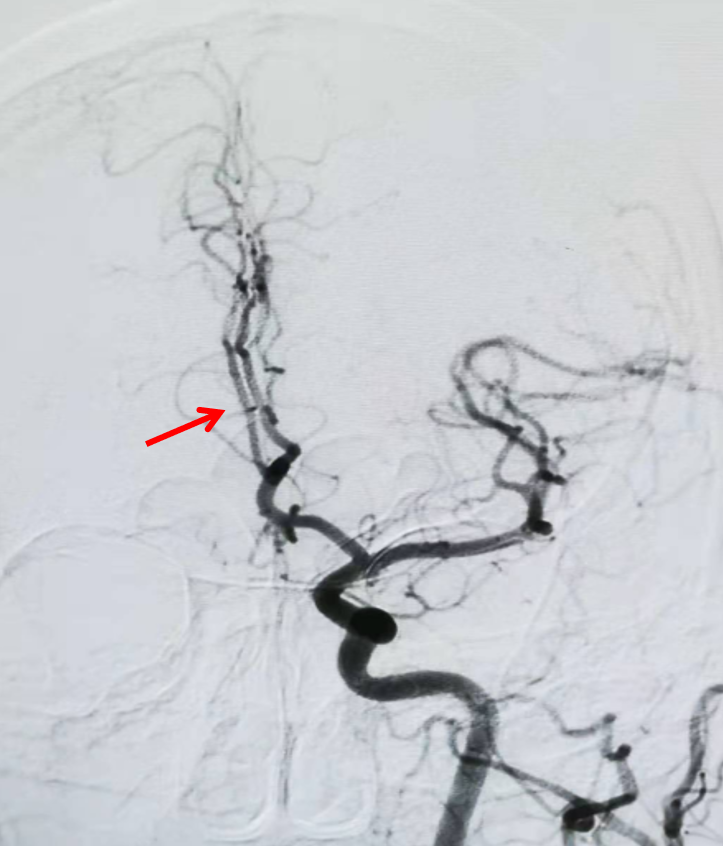

将1.5mmX10mm赛诺Neuro LPS™球囊沿微导丝引导至闭塞血管处(左图),感觉球囊稍短,分段缓慢(40秒)扩张至3atm,持续30秒后缓慢泄压后造影,可见血管部分再通(右图),但撤出球囊后前向血流不能维持。

将2.0mmX15mm的赛诺Neuro LPS™球囊沿微导丝引导至闭塞血管两端(左图),40秒缓慢扩张至3atm,持续40秒后缓慢泄压后造影,可见血管部分再通良好(右图)。

将1.5mmX10mm赛诺Neuro LPS™低压球囊沿微导丝引导至闭塞血管处,扩张至3atm,持续30秒后缓慢泄压后造影,可见血管部分再通(右图)。1

将2.0mmX15mm的赛诺Neuro LPS™低压球囊沿微导丝引导至闭塞血管两端,40秒缓慢扩张至3atm,持续40秒后缓慢泄压后造影,可见血管部分再通良好。